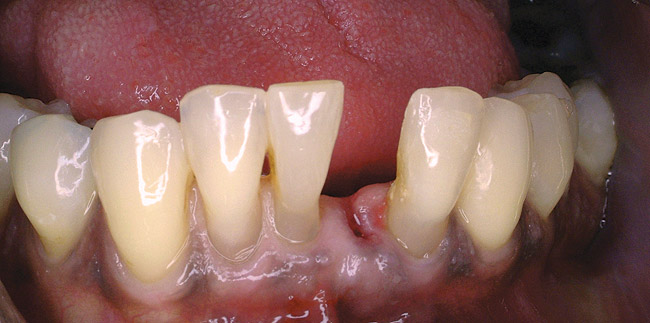

Figure 5a  Radiograph of severe periodontal bone loss on the mandibular left central incisor.

Figure 5a

Figure 5b  Facial view of the periodontally compromised central incisor.

Figure 5b